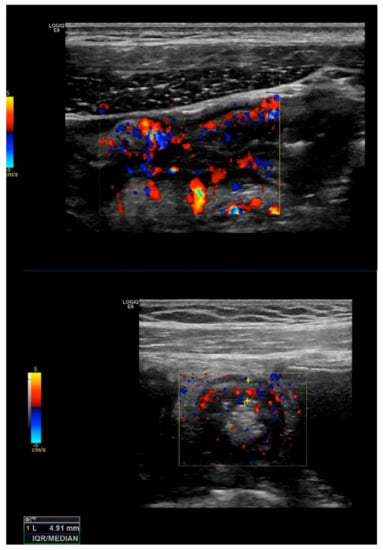

Bowel vascularization or bowel wall flow (BWF): vascularization can be measured at the thickened segments, by color or power Doppler US, using special presets of the machine optimized for slow flow detection []. The color Doppler flow is most widely measured by the Limberg score, which is a semi-quantitative score: [] grade 0 represents a normal bowel wall with no thickening, well-delineated mural stratification, and no mural flow (no color Doppler signal); grade 1 is defined by a thickened bowel wall without vascular signals, grade 2 by the presence of short stretches of vascularity, grade 3 by the presence of longer stretches of vascularity, and grade 4 by vascular signals extending into the surrounding mesentery (see Figure 3).

Figure 3.

Bowel vascularization: Bowel wall vascularization can be measured by color or power Doppler US. The Limberg score is widely used for the assessment of mural and extramural flow. In the picture, an increased bowel vascularization (Limberg score grade 3) can be visualized in the inflamed bowel.